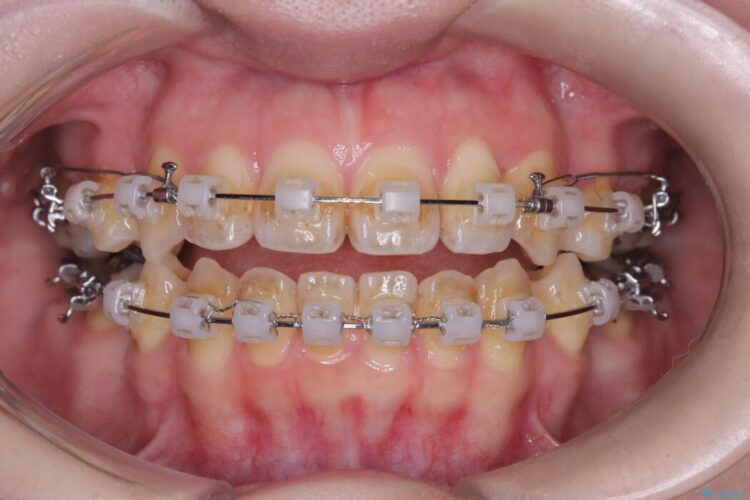

- 矯正装置:ワイヤー矯正(クリア装置)

気になっていたガタつきや開咬が改善され、見た目だけでなく咬み合わせの機能面も大きく向上し、大変ご満足いただけました。

また、治療期間も比較的短期間で終了することができました。